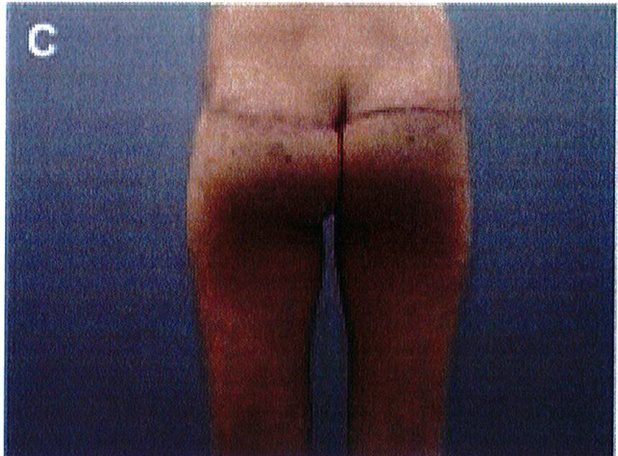

Hình. 11. (A, B) Bệnh nhân nữ 59 tuổi với vùng da mông chùng và xệ. (C,D) Hai năm sau phẫu thuật tạo hình thành bụng và tạo hình mông bằng phương pháp purse-string.Bênh nhân này bị tách vết mổ, sau đó đã đươc điều tri liền seo